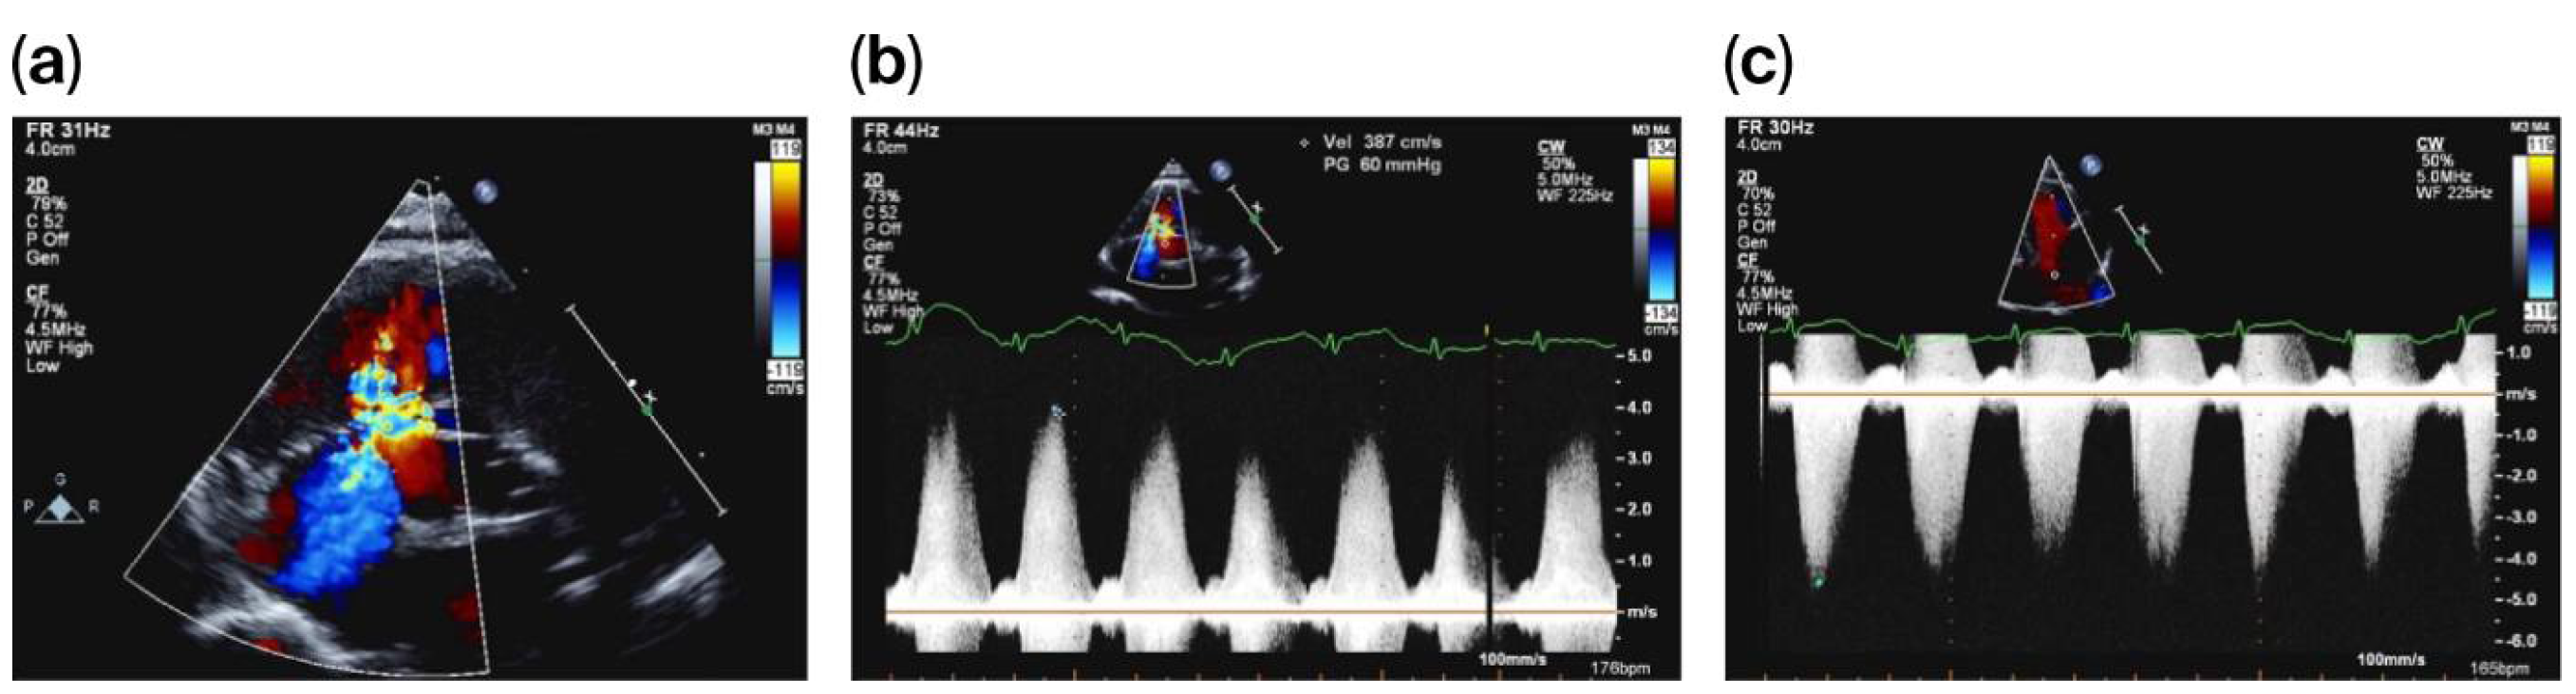

On day 20 of life, and due to a heart murmur on auscultation, TnECHO was requested. At our center, we perform TnECHO using a Philips iE33 Ultrasound Machine with a high-frequency 12 MHz phased-array probe (Figure 1). Echocardiography findings revealed a large peri-membranous ventricular septal defect (PMVSD) measuring approximately 4 mm, with left-to-right restrictive flow, with a peak gradient of 4 m/s, as shown in Figure 2. Biventricular systolic function was normal. Echocardiographic markers of pulmonary hypertension were reassuring and revealed a rounded intraventricular septum during systole (systolic left ventricular eccentricity index of 1), demonstrating a parabolic mean pulmonary artery flow Doppler pattern, with a pulmonary artery acceleration time to right ventricular ejection time (PAAT/RVET) ratio of 0.35 and a right ventricular output of ~400 cc/k/min. Tricuspid annular plane systolic excursion (TAPSE) was 8.5 mm, right ventricular fraction area change (RVFAC) was 40%, and tricuspid valve S’ (TV S’) was 5 cm/s. However, there was a significant tricuspid regurgitation jet with a peak velocity of 4 m/s, estimating a right ventricular peak systolic pressure of 70 mmHg, which is at the systemic level. Of note, this regurgitation jet was eccentric, adjacent to the VSD jet, as shown in Figure 2.

Figure 2. PMVSD with adjacent eccentric tricuspid regurgitation (a), with VSD Doppler (b) and tricuspid regurgitation Doppler (c).